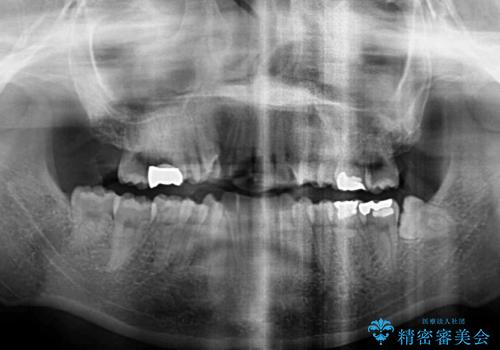

- 上下の八重歯を気にして来院された患者様です。

上下ともに八重歯の後ろの歯を1歯ずつ抜歯し、補助装置(リンガルアーチ)を用いて八重歯の位置を改善し、その後インビザラインにより矯正治療を行うこととしました。

途中海外留学をされたため、治療期間は長くなりましたが、事前に補助装置やワイヤー装置を併用したことで、きれいな歯列に仕上げることができました。